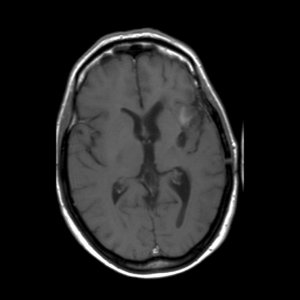

Een astrocytoom graad III groeit onbehandeld snel door in het omliggende hersenweefsel; de ziektegeschiedenis is daarom meestal relatief kort. De meeste patiënten zijn tussen de 30 en 50 jaar oud, iets vaker mannen dan vrouwen. Een MRI toont meestal een grillige, slecht begrensde tumor die met contrast kan aankleuren. De diagnose moet gesteld worden door onderzoek van het weefsel.

'Hoe is het mogelijk, dit kan niet, dit is bizar, zoiets heb ik nog nooit gezien maar het is waar'. Dit waren de woorden van de neuro-oncoloog. Mijn vriendin Ineke en ik bogen ons naar haar computer waar het onverklaarbare resultaat stond. Op de MRI-scan was te zien dat de kwaadaardige tumor zich had teruggetrokken. De tumor had een donkere holte met een grillige tumorrand achtergelaten. De neuro-oncoloog benadrukte nog eens dat het echt heel bijzonder was en dat zij en de radioloog voor een raadsel stonden. Ik vroeg haar wat dit betekende voor de prognose van mijn levensverwachting. Ze zei dat er nog één of misschien zelfs twee jaar zou bijkomen. Meer durfde ze er ook niet over te zeggen.

De MRI scans van 2006 en 2007 zijn niet correct geïnterpreteerd. Wat toen als tumorgroei werd gezien blijkt nu een reactie van de bestraling te zijn. De chemokuur was overbodig omdat de tumor niet groeide. Wat je nu ziet is de tumor die enigzins gegroeid lijkt, maar dat is niet zeker. Als het zeker is moet je overwegen om opnieuw bestraald te worden. Meer patienten zijn ook met de verkeerde boodschap (dat de tumor groeit) naar huis gegaan,ook in andere ziekenhuizen.

Je moet je realiseren dat een MRI een plaatje is waarop een proces zichtbaar wordt oa door aankleuring met contrast. Met een MRI kun je dus vervolgen of een “proces” groter of kleiner wordt. Maar een MRI geeft geen inzicht in de aard van het proces, je weet niet welke cellen toegenomen zijn.

De MRI na de bestraling liet zien dat het ‘proces”in jouw hersenen gegroeid was. Omdat men wist met een kwaadaardige tumor te maken te hebben, is daaruit de op dat moment voor de hand liggende conclusie getrokken dat de radiotherapie helaas niet geholpen had. Na de aanname dat de radiotherapie niet geholpen leek te hebben heeft men het voorstel voor chemotherapie gedaan. Naar mijn mening op goede gronden. Helaas blijkt vaker dat als de tijd verstrijkt je voor verrassingen kan komen te staan zoals ook in jouw geval. Toen na een hele tijd een MRI werd herhaald bleek ‘het proces’in de hersenen eerder kleiner te zijn geworden dan de groei die men eigenlijk had verwacht. Op dat moment heeft men de conclusie moeten trekken dat de toename van het proces na de bestraling dus een gevolg moet zijn geweest van de bestraling een soort oedeem (zwelling) tgv de straling. Deze conclusie is echter alleen te maken door het beloop in de tijd en deze conclusie was niet te maken in een eerder stadium.

Dit betekent ook dat het vanaf nu wel zinnig is om met enige regelmaat de MRI te vervolgen. Mocht er ooit weer op de MRI een toename van het proces gezien worden dan is namelijk opnieuw radiotherapie een goede behandelingsmogelijkheid. (chemo ligt wat minder voor de hand omdat je dat slecht hebt verdragen).Je moet alleen pas overwegen te gaan behandelen als op de laatste MRI duidelijk een groei te zien is van het proces, weet jij of de laatste MRI een verschil aangaf met de vorige? Als je het goed vindt kan ik in het UMCG ook de gemaakte MRI’s van jou bekijken als het jou niet helemaal duidelijk is geworden.

Op de scan was sprake van enige aankleuring, maar de neuro-oncoloog is er van overtuigd dat het geen tumorgroei is maar nog een oedeem van de bestraling. Volgens haar duwt de tumor andere cellen aan de kant en een oedeem doet dat niet. Bovendien is de aankleuring ook a-typisch wat betekent dat hij niet als ronding begint en juist dát hoort bij een glioom.